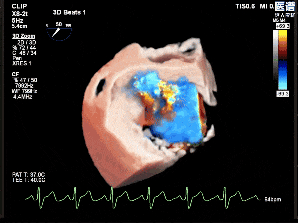

术前超声影像

3D

3D彩

术前超声